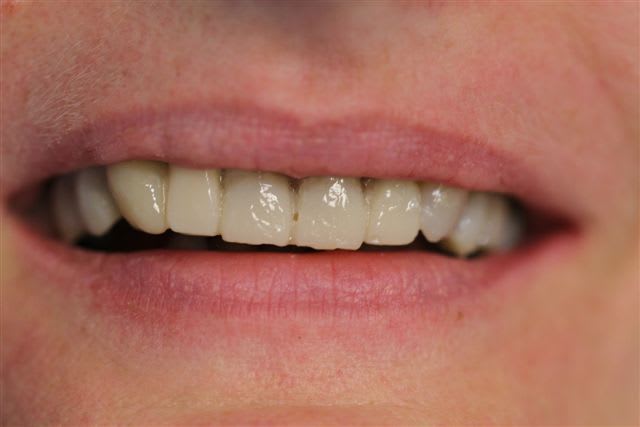

N'hésitiez pas çà me donner votre avis, patiente 47 ans ne supporte plus ses antérieurs, maquillées à la résine il y a quelques années.

Pas de demande concernant l'occlusion, ni les postérieurs, à fait des économies et veux s'offrir "un sourire", sur fond propre budget envisageable au départ 4000€

Postérieur bas (16/08)et haut (14/09) en place, essayage des Emax avec "cutback".

Pour la teinte la patiente exige B1, sans maquillage, elle n'a pas attendu 47 ans pour que ça ne soit pas Blanc de blanc, alors là dessus j'ai cédé.